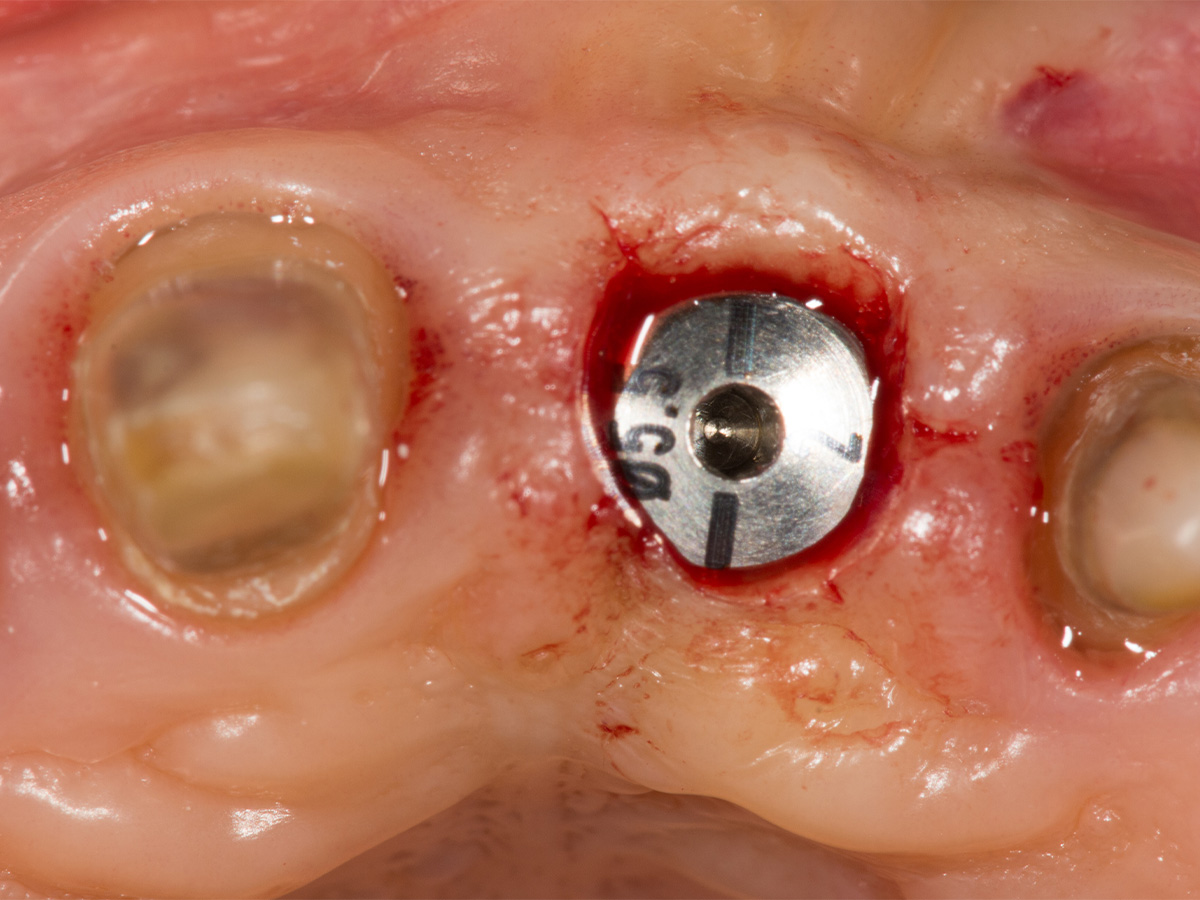

Abbildung 12

Implantation: Gutes Knochenvolumen in horizontaler und vertikaler Dimension.

Abbildung 13

Implantation in optimaler prothetischer Ausrichtung möglich, da ausreichendes knöchernes Angebot in vertikaler und horizontaler Dimension.